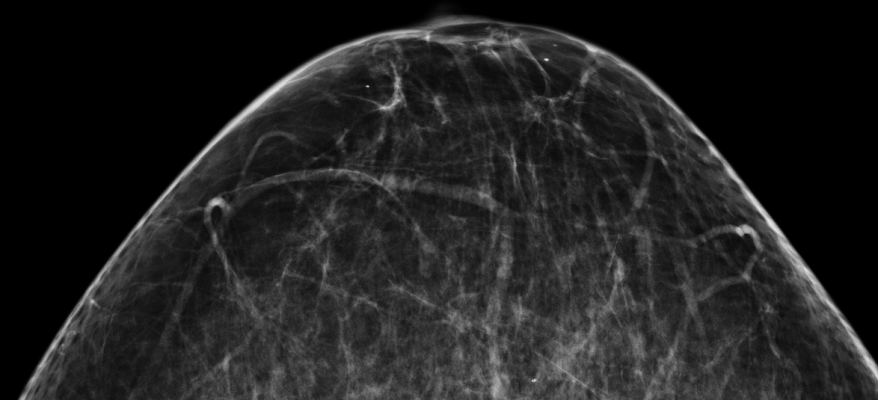

August 22, 2017 — When to initiate screening for breast cancer, how often to screen, and how long to screen are questions that continue to spark emotional debates. A new study compares the number of deaths that might be prevented as a result of three of the most widely discussed recommendations for screening mammography. Published early online in Cancer, a peer-reviewed journal of the American Cancer Society, the findings may provide valuable guidance to women and their physicians about choosing a screening regimen.

To uncover insights that might help women make informed choices about mammography screening, researchers led by Elizabeth Kagan Arleo, M.D., of Weill Cornell Medicine and New York-Presbyterian, and R. Edward Hendrick, Ph.D., of the University of Colorado School of Medicine, used computer modeling to estimate the possible effects of three schemes: annual screening starting at age 40 years, annual screening at ages 45 to 54 years and then biennial screening at ages 55 to 79 years, and biennial screening at ages 50 to 74 years.

The investigators estimated how many breast cancer deaths might be prevented with the different screening schemes. The team found that the recommendation of annual screening starting at age 40 would result in the greatest reduction in breast cancer-specific deaths — a nearly 40 percent reduction in deaths due to breast cancer, compared with 23 percent to 31 percent reductions with other recommendations.